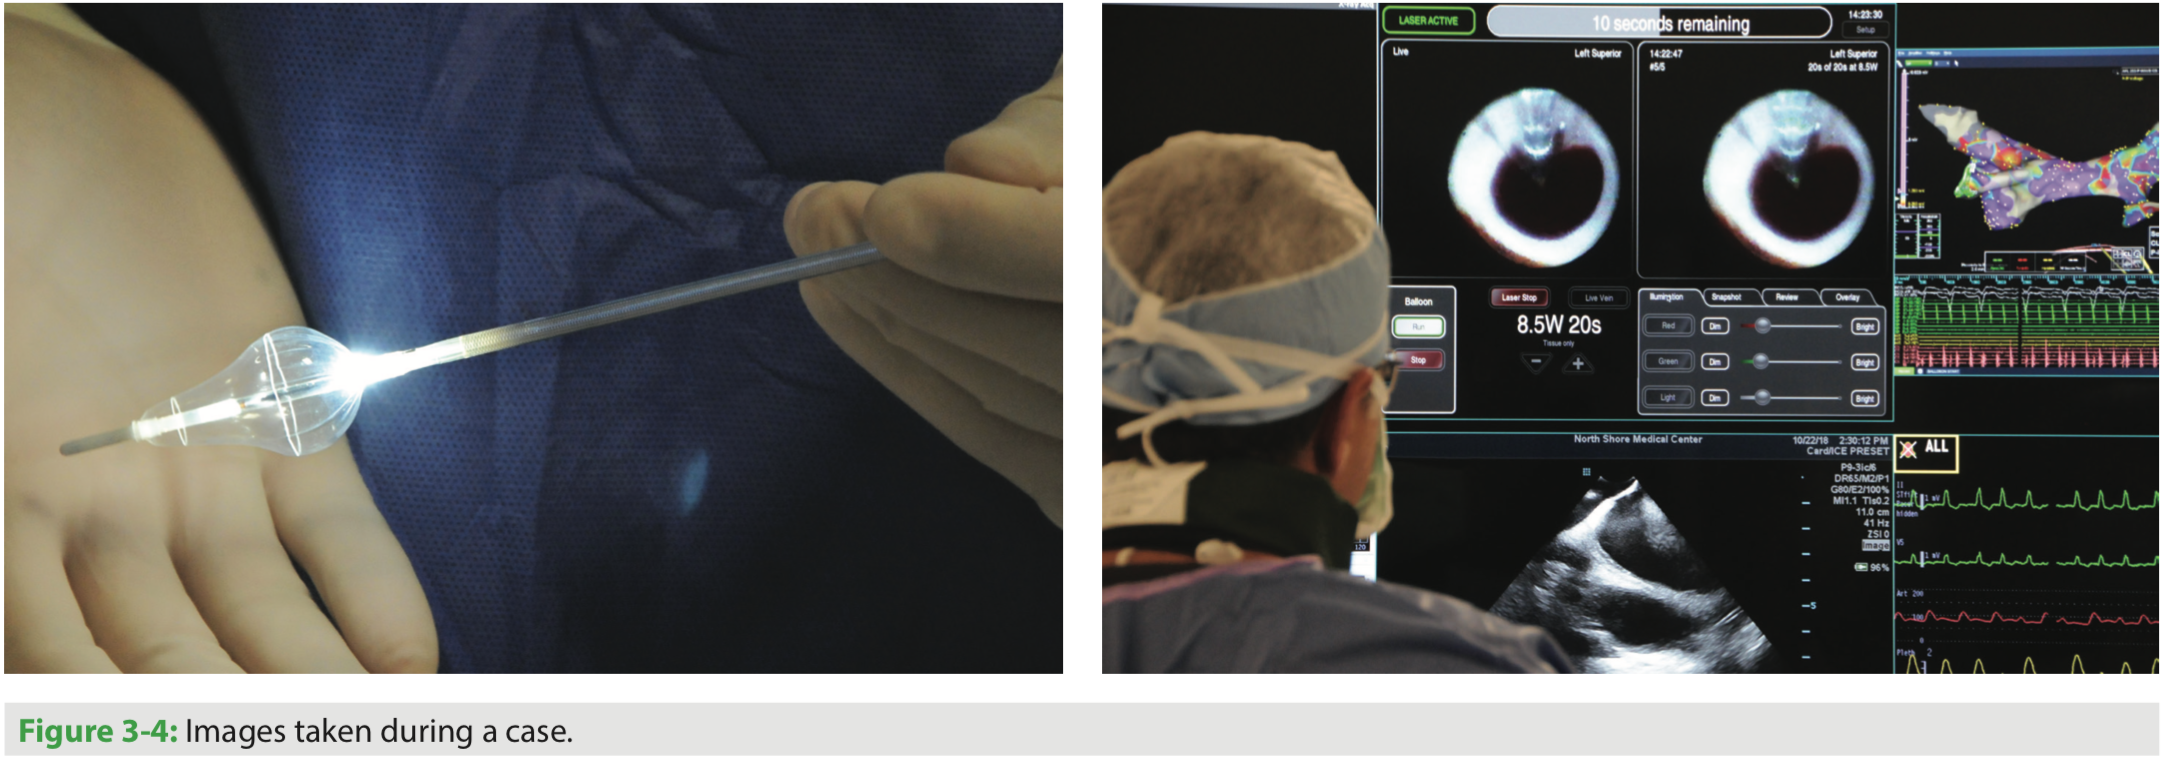

a The picture of the X3 laser balloon ablation system. The green arrow Endoscopic Laser Balloon Ablation System The heartlight x3 endoscopic cardiac ablation system with the excalibur balloon enables physicians to achieve stable contact with direct tissue visualization. The heartlight endoscopic ablation system demonstrated similar efficacy as irrigated radiofrequency current ablation for atrial fibrillation ablation. The endoscopic laser ablation system (heartlight ®, cardiofocus, inc.,. The endoscopic laser balloon ablation system (heartlight® eas, cardiofocus inc.) is the first. Endoscopic Laser Balloon Ablation System.